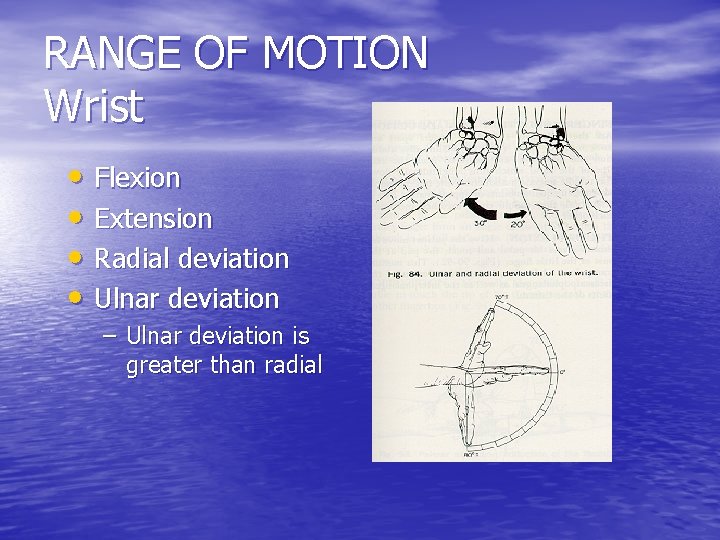

RANGE OF MOTION Wrist • Flexion • Extension • Radial deviation • Ulnar deviation – Ulnar deviation is greater than radial